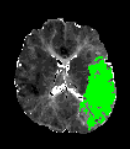

南京市第一医院是国家卫生健康委首批高级卒中中心,设有独立的神经内科急诊及脑血管病绿色诊疗通道。接诊的侯建康主治医师第一时间启动绿通,完善了头部磁共振及血管成像检查,明确了王先生急性缺血性脑梗死的诊断,而梗死原因是王先生脑内两根非常重要的血管(左侧颈动脉和左侧大脑中动脉)发生了堵塞(见图1)。

图1